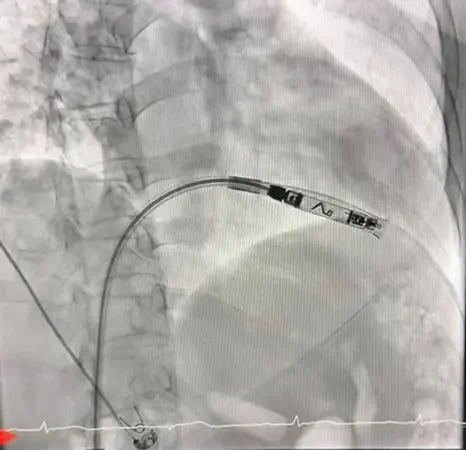

ศูนย์หัวใจ โรงพยาบาลหาดใหญ่ ประสบความสำเร็จในการรักษาผู้ป่วยโรคหัวใจเต้นช้าผิดจังหวะชนิดสมบูรณ์ (Complete Heart Block) ด้วยการใส่เครื่องกระตุ้นหัวใจชนิดไร้สาย (Leadless Pacemaker) ผ่านสายสวนหลอดเลือด ซึ่งเป็นเทคโนโลยีทางการแพทย์สมัยใหม่ และนับเป็นครั้งแรกของโรงพยาบาลในสังกัดสำนักงานปลัดกระทรวงสาธารณสุข ที่สามารถดำเนินการรักษาด้วยวิธีนี้ได้สำเร็จ

ผู้ป่วยเป็นหญิงอายุ 56 ปี ได้รับการวินิจฉัยว่าเป็นโรคหัวใจเต้นช้าผิดจังหวะชนิดสมบูรณ์ (Complete Heart Block) ซึ่งจำเป็นต้องใส่เครื่องกระตุ้นหัวใจเพื่อช่วยควบคุมจังหวะการเต้นของหัวใจ โดยคณะแพทย์ได้เลือกใช้เครื่องกระตุ้นหัวใจชนิดไร้สาย (Leadless Pacemaker) ซึ่งเป็นเทคโนโลยีใหม่ล่าสุด ทำการใส่ผ่านสายสวนหลอดเลือดเข้าสู่หัวใจโดยตรง

เทคโนโลยีดังกล่าวมีข้อดีคือ ไม่มีสายไฟเชื่อมต่อกับตัวเครื่อง ลดความเสี่ยงต่อการติดเชื้อ ลดภาวะแทรกซ้อนจากสายเครื่องกระตุ้นหัวใจ และช่วยให้ผู้ป่วยฟื้นตัวได้เร็วขึ้น